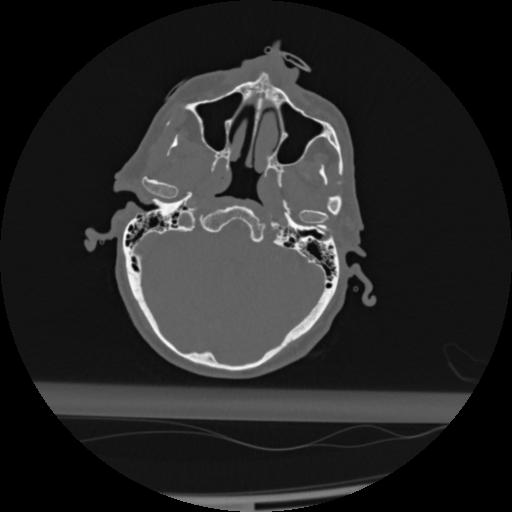

22 ANGIO,CE,Vol,0.5,ANGIO,,